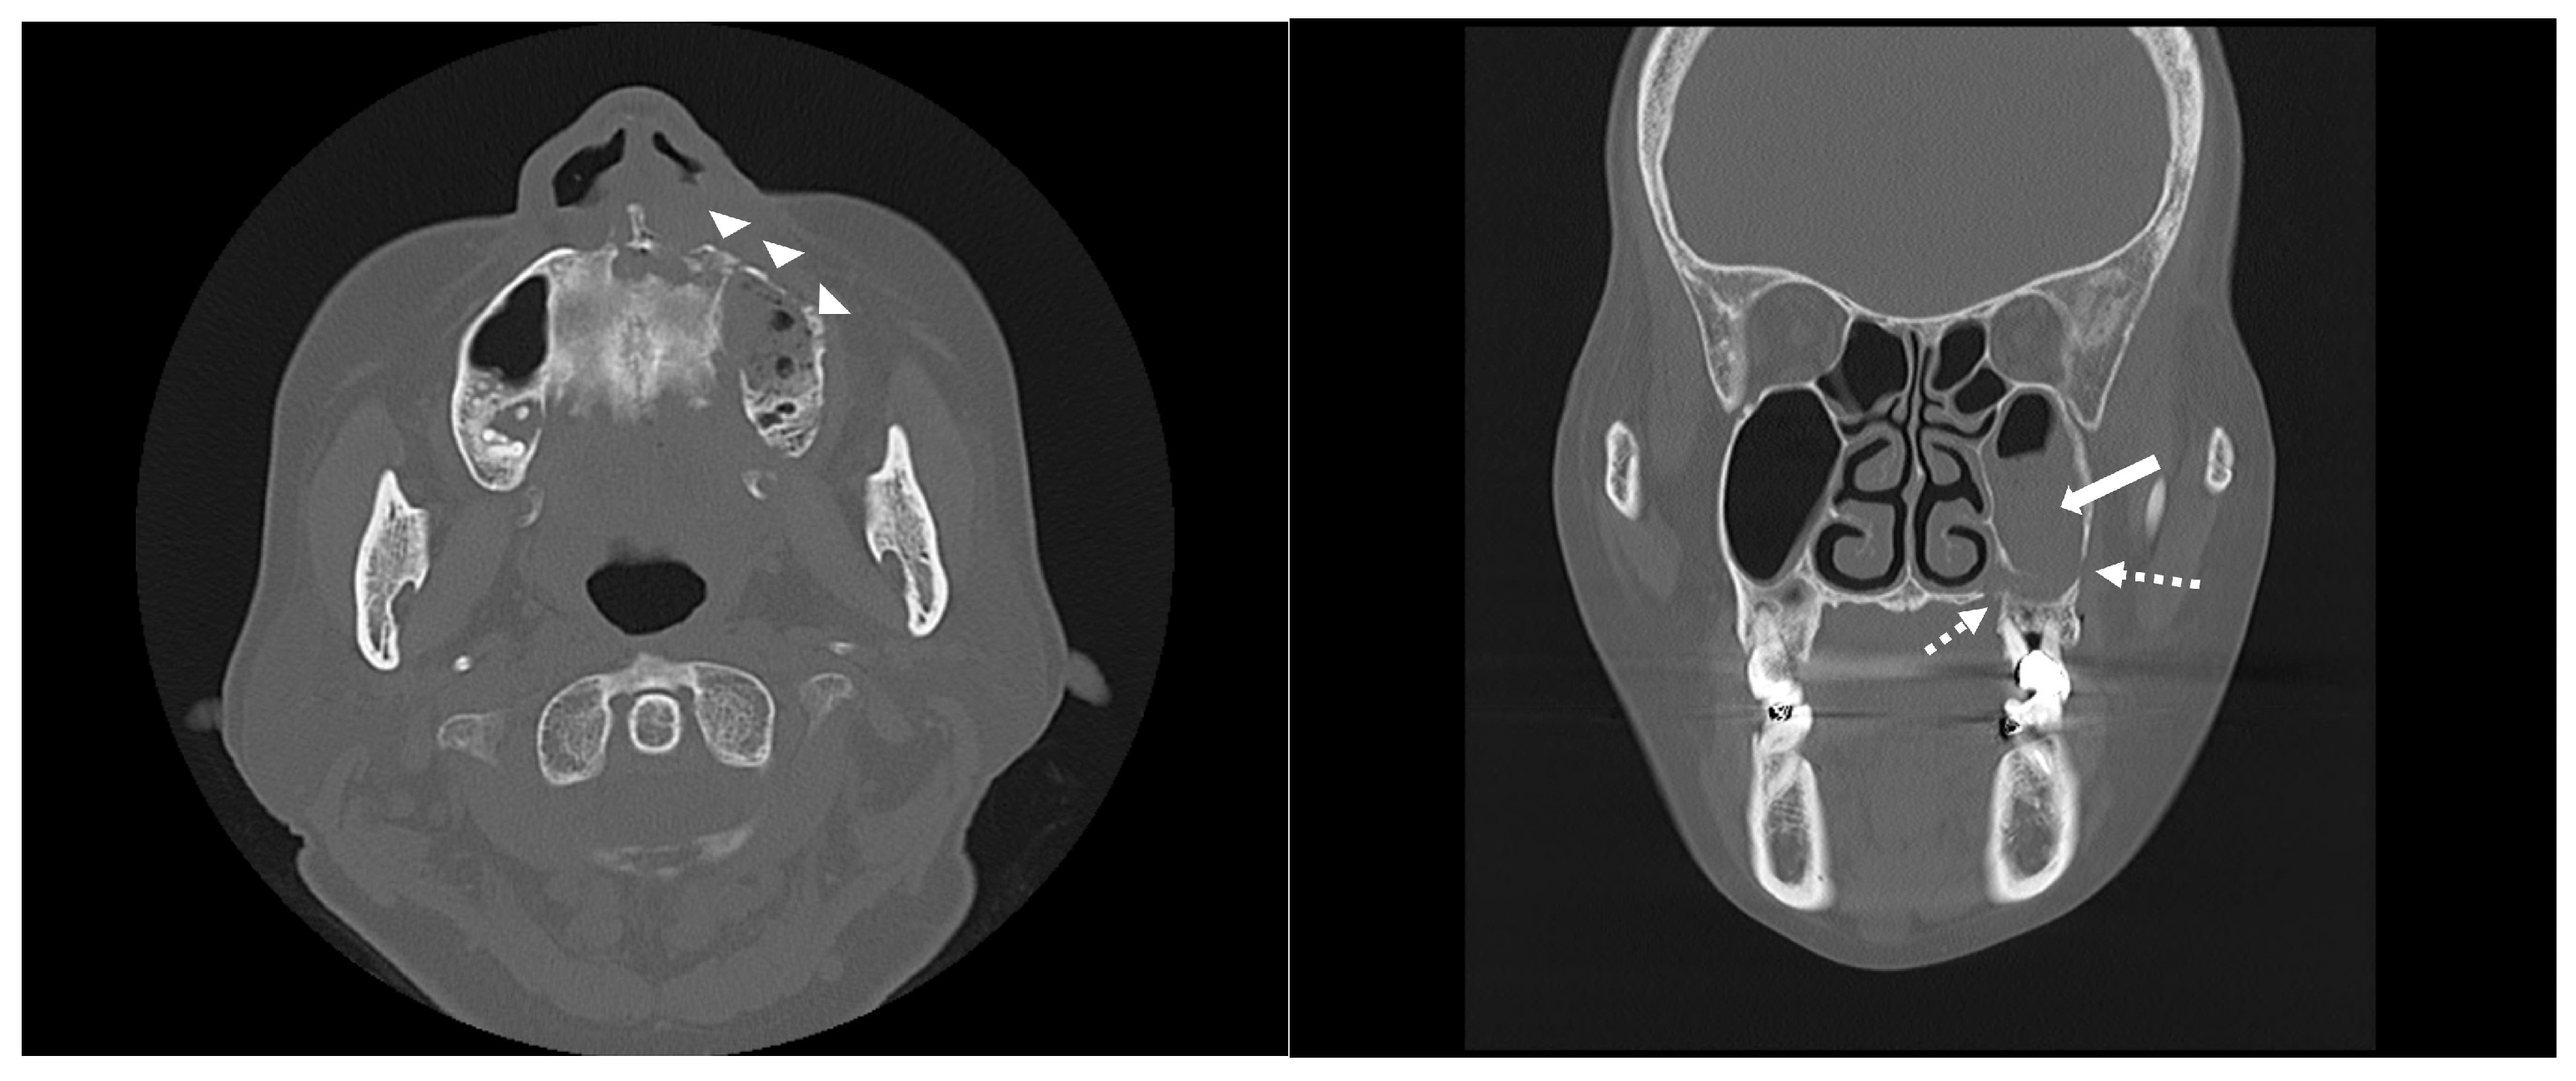

2. Case Report